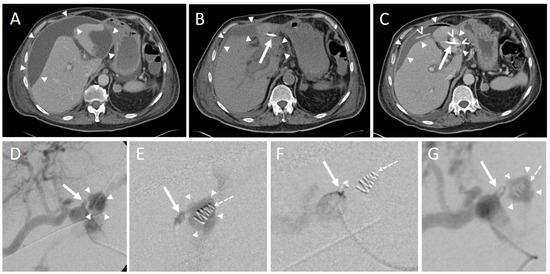

Focussing on the entire intervention DLP (median (25%, 75% quartile)) was 944.5 (730.8, 1177.0) mGy*cm between 2004–2010 and 621.5 (452.8, 878.5) mGy*cm between 2011–2017, corresponding to a significant decrease (p < 0.05). Accordingly, all examination parts of the CT intervention differed significantly (p < 0.05): Radiation dose in pre-interventional scans was 472 (329, 635) mGy*cm in the years 2004–2010 and 343.0 (215.8, 472.5) mGy*cm in the years 2011–2017. In the years 2004–2010 the DLP of the intra-interventional scan was 116.0 (67.0, 207.0) mGy*cm and 48.5 (26.8, 82.3) mGy*cm in the years 2011–2017. DLP analysis with regard to the post-interventional control scan yielded 316 (255, 389) mGy*cm (years 2004–2010) vs. 245 [169, 331] mGy*cm (years 2011–2017).

Comparing both time intervals, CT fluoroscopy was characterized by the most pronounced decrease, corresponding to a reduction of −58.2% of the median value (Figure 5).

Figure 5. Median radiation dose between 2004–2010 and 2011–2017. Boxplots display elements of the interventional CT scan and the entire procedure.